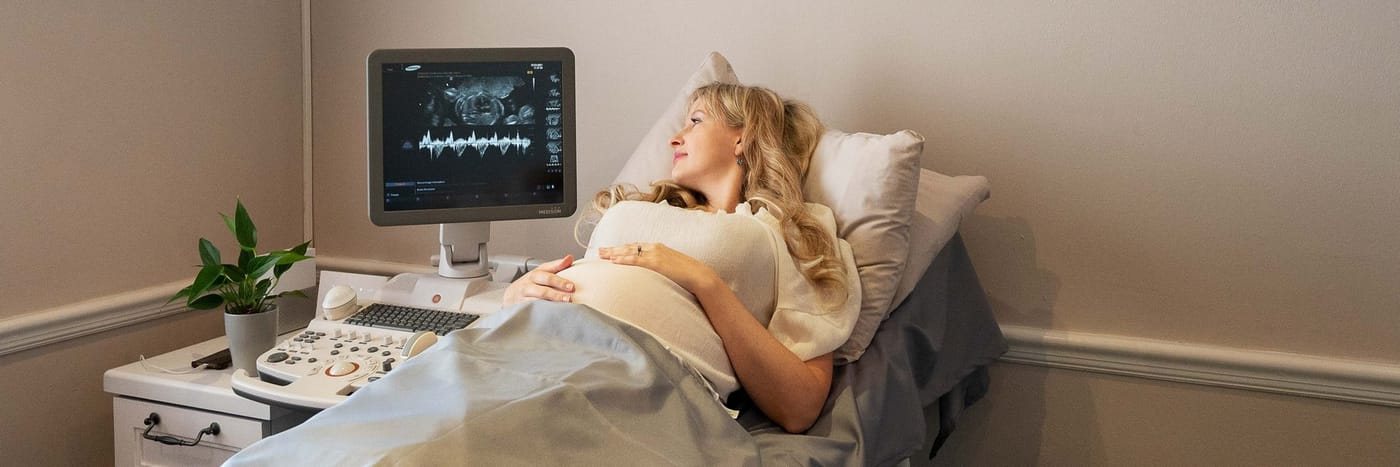

Tummy Time 4D Ultrasound Studio

Come and Meet

Your Baby

Fetal ultrasounds throughout your pregnancy —

from first heartbeat to first smile.

About Tummy Time Pregnancy Scan Studio in Somerset West

Founded in 2012 by Kirsten Kotze, Tummy Time has been sharing in the joy of parenthood for over a decade.

Kirsten completed her B-Tech Ultrasound accreditation at Groote Schuur Hospital in 2009 and brings over 15 years of experience in the ultrasound industry. What started with a passion for revealing baby’s gender has grown into a full-service fetal ultrasound practice.

“I wanted to share in the joy experienced when revealing Baby’s Gender. My vision is to assess baby for mom’s peace of mind and then enjoy absolutely everything in that moment.” — Kirsten Kotze, Founder

Over the years, Kirsten identified a growing demand for fetal anatomy ultrasounds and expanded the service offerings to include dating scans, NT scans, detailed anatomy assessments, and the signature 4D experience.